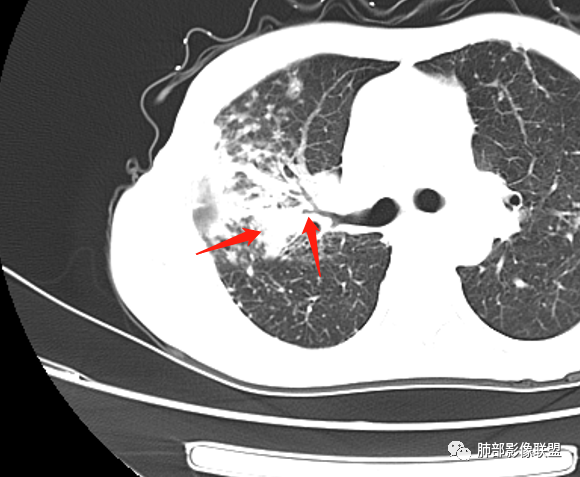

就这里不让人放心,是占位吗?支气管是截断的,没有凹陷或者突出阻断,阻断前稍扩张

患者老年女性,亚急性起病,主要症状表现为咳嗽、咳痰半月余,查体:双现呼吸音粗,双肺可闻及痰鸣音。胸部CT:双上肺胸膜下可见多发小叶实变影,双上肺可见多发小叶中心性结节及小叶间隔增厚,右上肺后段可见亚段性实变影,内见多发空洞,前段可见GGO及树芽征,后段局部支气管闭塞,肺门淋巴结肿大并钙化。病灶整体:有气道、间质播散,一元论考虑肺结核合并支气管结核可能性大,建议好好查痰;这样病灶:明显实变+空洞+气道播散,若是结核,痰涂片找到抗酸杆菌应该没问题。建议支气管镜检查助诊,了解有无支气管结核及合并腺癌的可能。

1、树芽征

2、多发结节,卫星灶

3、小叶间质增厚,有索条影

4、反晕征

1.双肺片状影、大小不等斑片影、结节影、树芽等,病灶密度偏高多钙化。

2.病灶上肺为主,胸膜下分布为主。双肺病灶明显不对称,右肺块状影较大。

3.纤维条索影广泛杂乱、牵拉,横向分布为主,这点给人也印象很深!

4.纵隔轻度右移。双肺门纵隔淋巴结增大钙化。